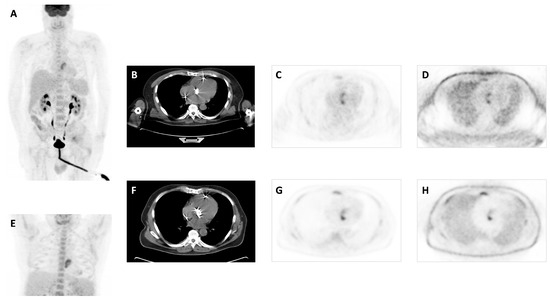

- Uptake suggestive of infection: intense elevation of 18F-FDG (hypermetabolism) of focal and/or heterogeneous type in relation to prosthetic material or cardiac lesions, identified in both corrected and uncorrected images. In the case of PVE, it was also required that the prostheses had been placed more than 3 months ago.

- Increased intensity in late acquisition compared to early acquisition was suggestive of infection.

- The sole appearance of increased focal or heterogeneous uptake in late acquisition was suggestive of infection.